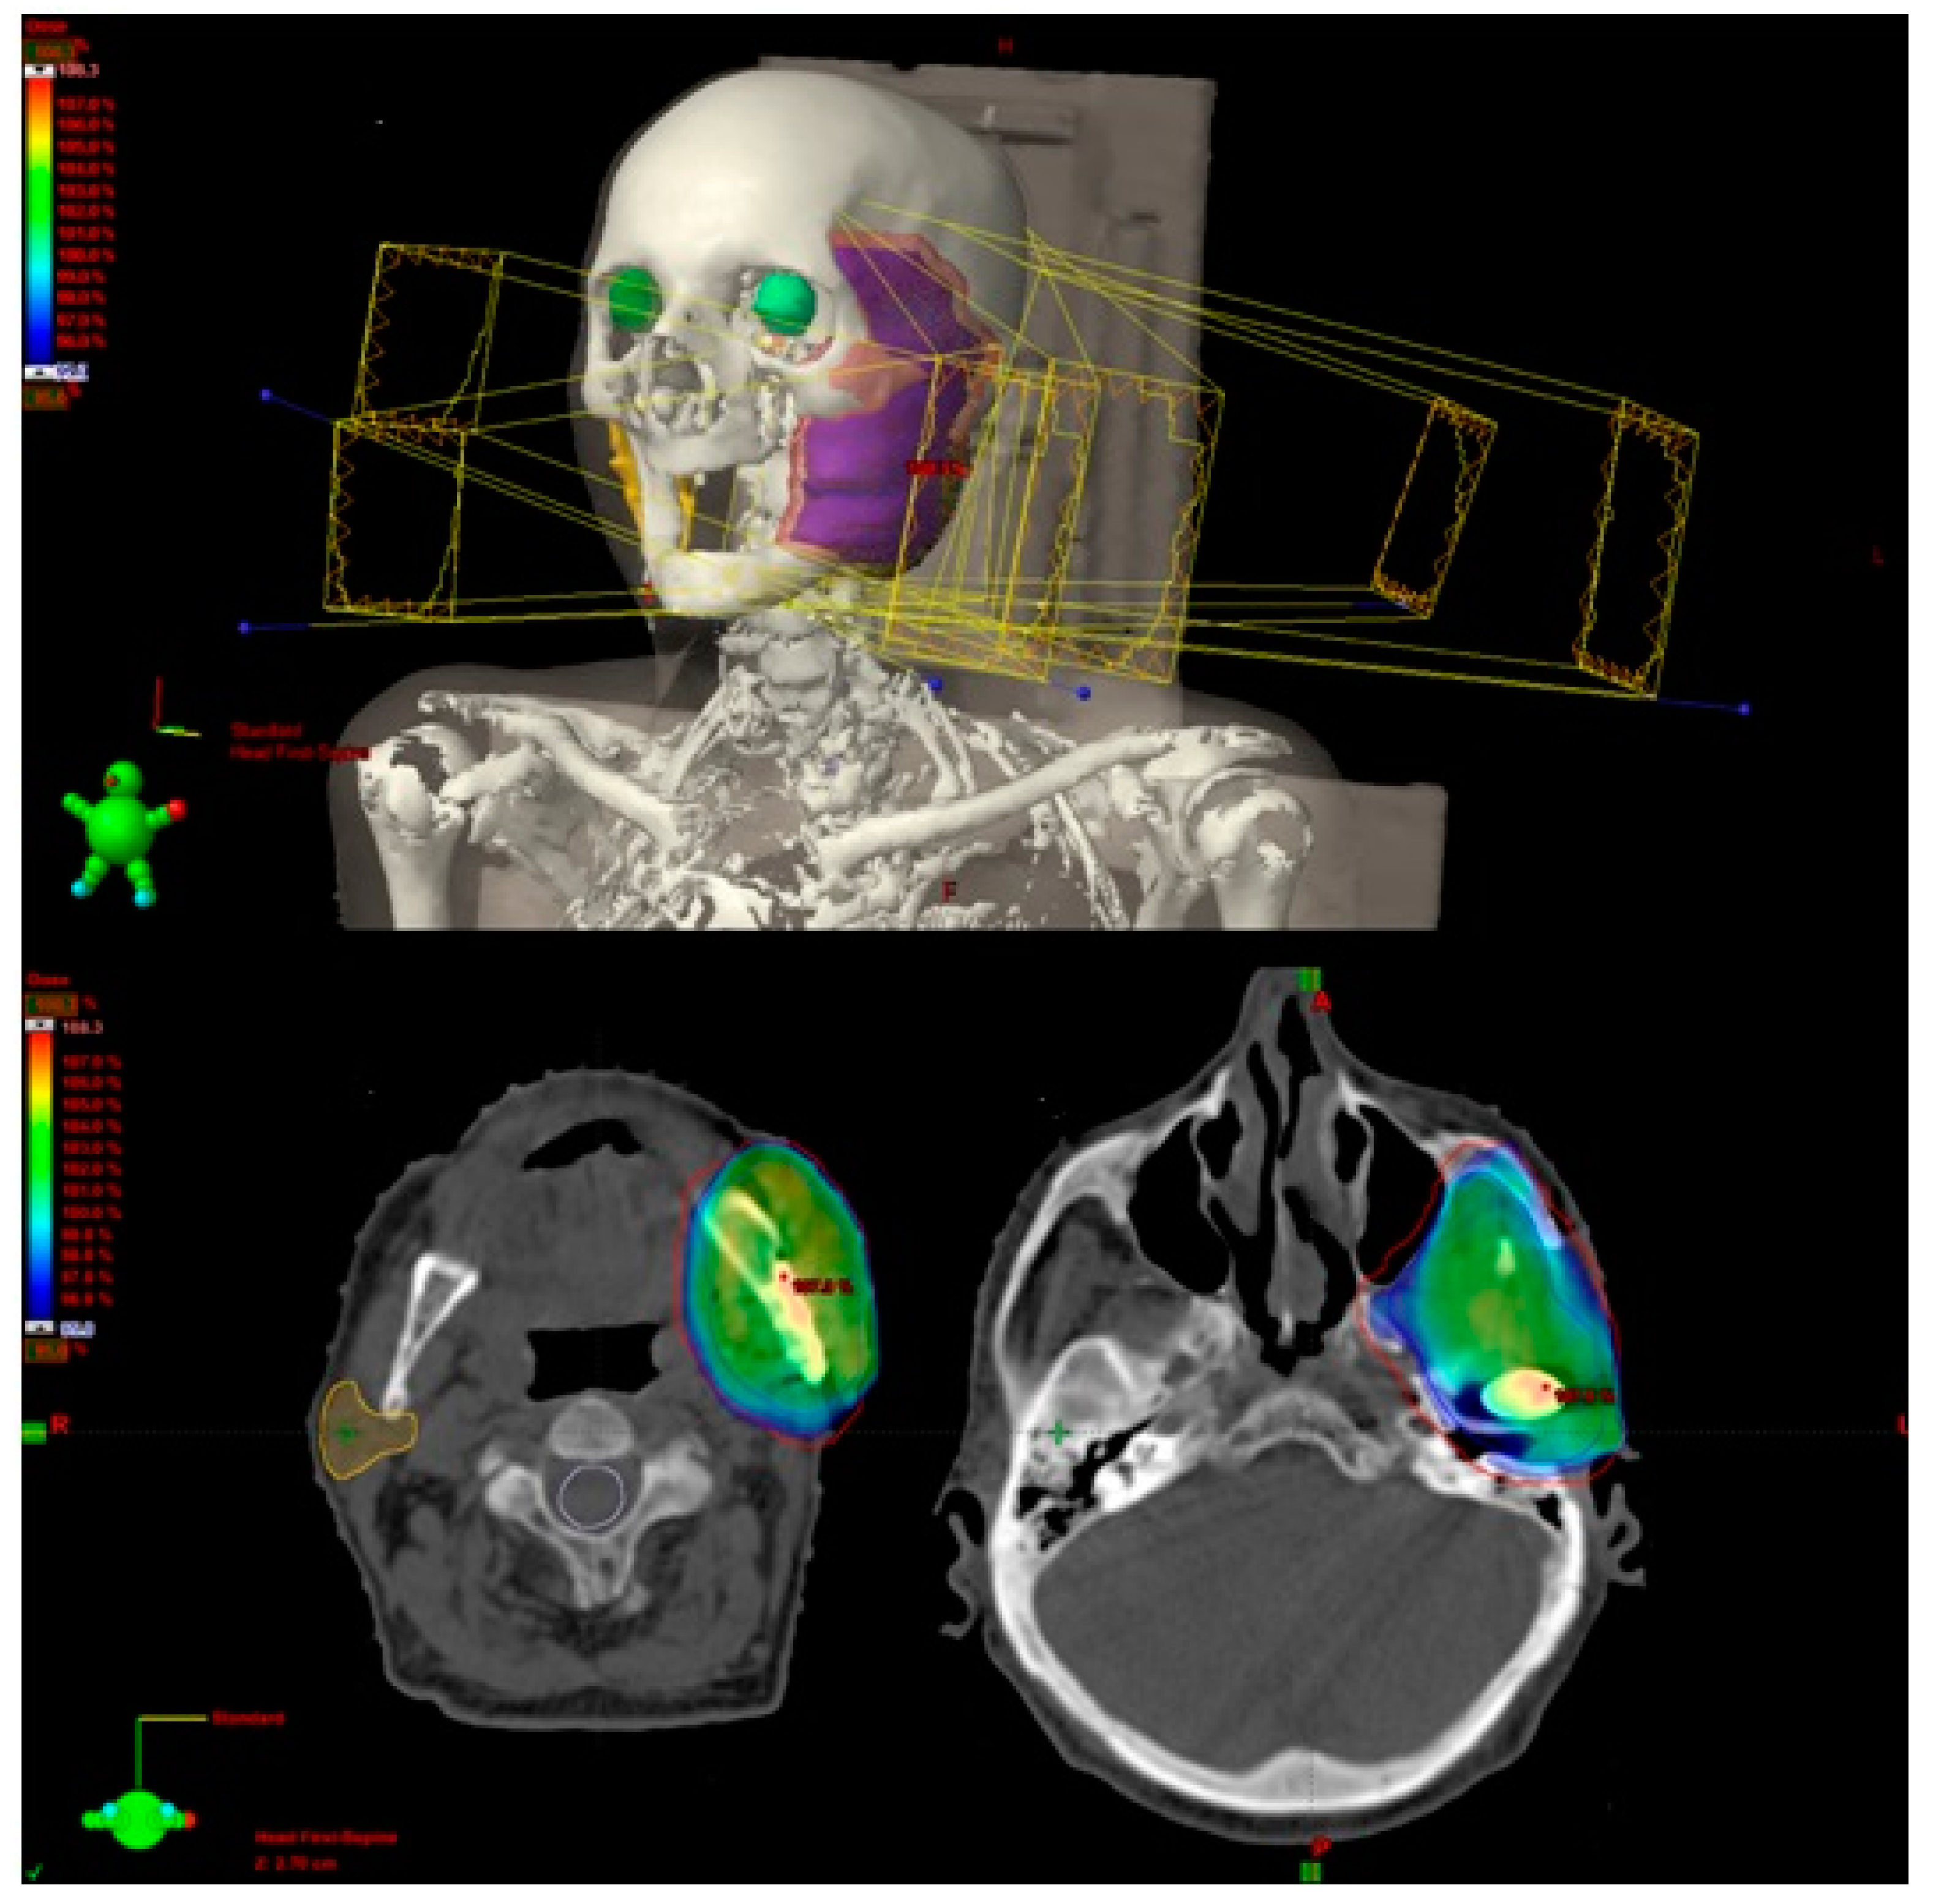

3. Results